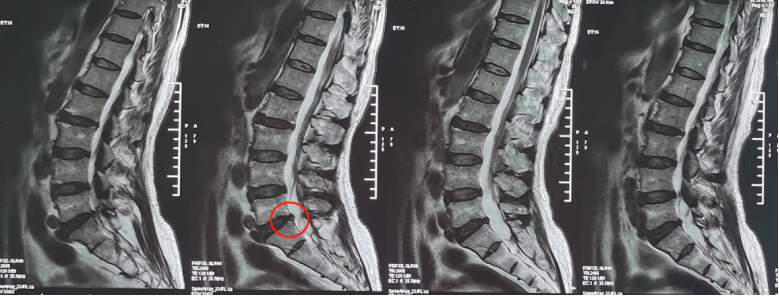

熊东主任接诊后,建议患者进行腰椎CT、核磁共振等影像检查和各项查体,结合各项检查结果,最终确诊患者为“腰椎间盘突出症(腰5/骶1,中央型)”。除此之外,患者还有相应水平的硬膜囊受压与腰椎骨质增生。

术前影像学资料:

“之前一直说是腰椎间盘突出症,我搞不明白,腰椎的问题,怎么让两条腿又疼又麻?”刘大爷在门诊时将自己的不解问了出来。熊东主任为他这样解释,“您的这种情况其实是正常的,腰椎间盘突出症不一定都会引起腰痛等症状。但是由于腰椎间盘突出会压迫到腰神经,腰神经掌管着下肢的运动和感觉,所以就会出现下肢的放射性疼痛、麻木、无力。一般来说,腰椎间盘突出症患者多出现一侧神经受压,常常表现为一侧下肢症状,但是您的片子上显示是中央型,两边的神经都有受压,所以双腿都出现了症状。”